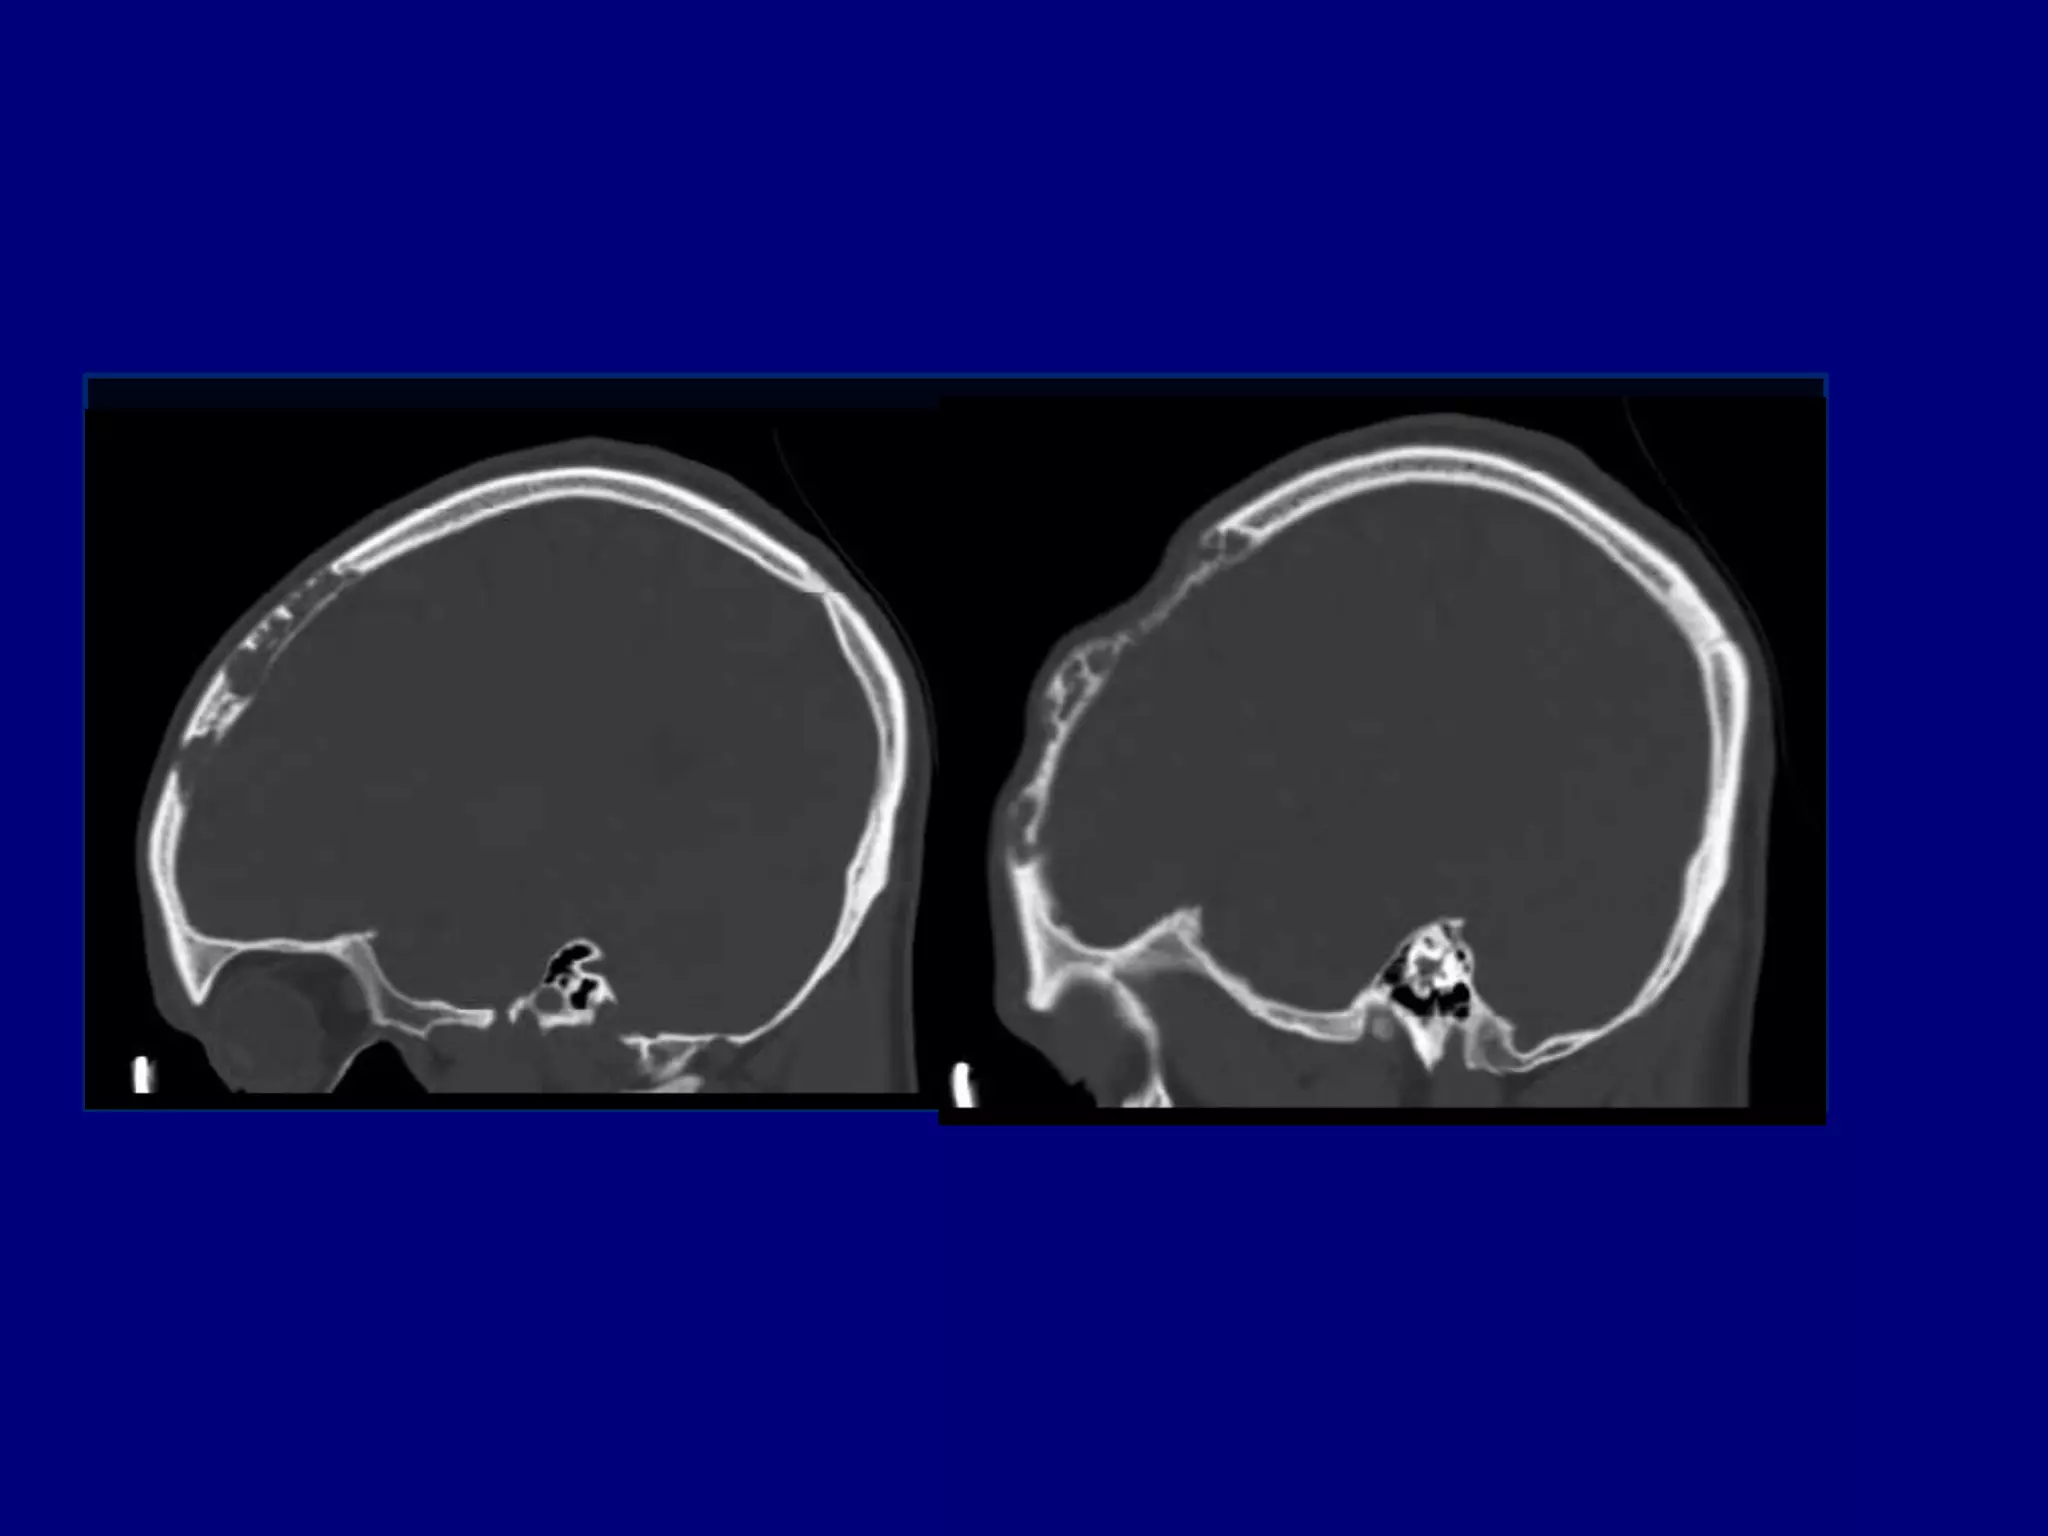

Computed Tomography

Magnetic Resonance Imaging

CT

Well defined skull defect with benign characteristics

 Thinning and disappearance of central portion and

absence of new bone formation